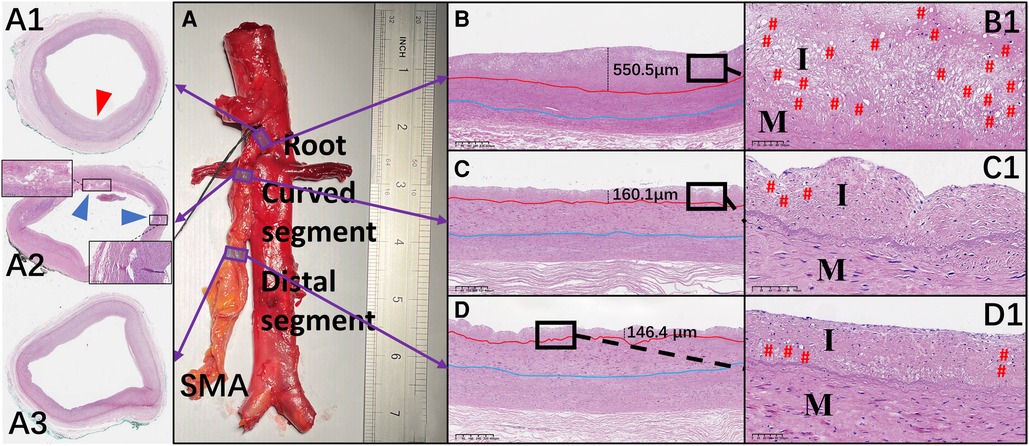

Hematoxylin and eosin–stained sections are shown in Figure 5. Crescent-shaped intimal thickening was observed at the root of the SMA (Figure 5A1). Foam cells with lipid droplets in the cytoplasm were more common in the intima at the SMA root than in other segments (Figures 5B1–D1). Translamellar mucoid extracellular matrix accumulation breaking through the lamellar units was observed in the media of the anterior wall at the curved segment of the SMA (Figure 5A2). At the distal segment of the SMA, the structure of the circumferential arterial wall was uniform, with no obvious degenerative changes (Figure 5A3).

Figure 5. Representative images of hematoxylin and eosin–stained sections of the superior mesenteric artery (SMA) wall and comparison of the mean thickness of each layer of the vascular wall in the different regions of the SMA. (A–D and A1–D1) Hematoxylin and eosin staining of the wall located at the root (A1), curved segment (A2), and distal end (A3) of the SMA. Thickening of the intima (red arrow) and translamellar mucoid extracellular matrix accumulation (blue arrows) can be observed. (B–D) The thickness of each intima is shown. (B1–D1) Local magnification of the images in B–D. # represents the location of foam cells. I, intima; M, media.

The mean thickness of the intima at the root of the SMA (388.5 ± 202.3 µm) was greater than that in the curved (243.8 ± 100.5 µm; p = .007) and distal (183.7 ± 88.0 µm; p < .001) segments. However, there was no significant difference in the mean thickness of the other 2 layers across the 3 locations of the SMA. In the curved segment of the SMA, the mean thicknesses of the intima (256.8 ± 118.4 µm), media (353.1 ± 37.6 µm), and adventitia (338.2 ± 107.2 µm) at the anterior wall were lower than the mean thicknesses of the intima (230.7 ± 83.2 µm; p = .58), media (473.7 ± 142.8 µm; p = .02), and adventitia (451.4 ± 191.8 µm; p = .12) at the posterior wall. There was no significant difference between the anterior and posterior walls in the mean thicknesses of the 3 layers at the other 2 locations of the SMA (Figures 6A–D).